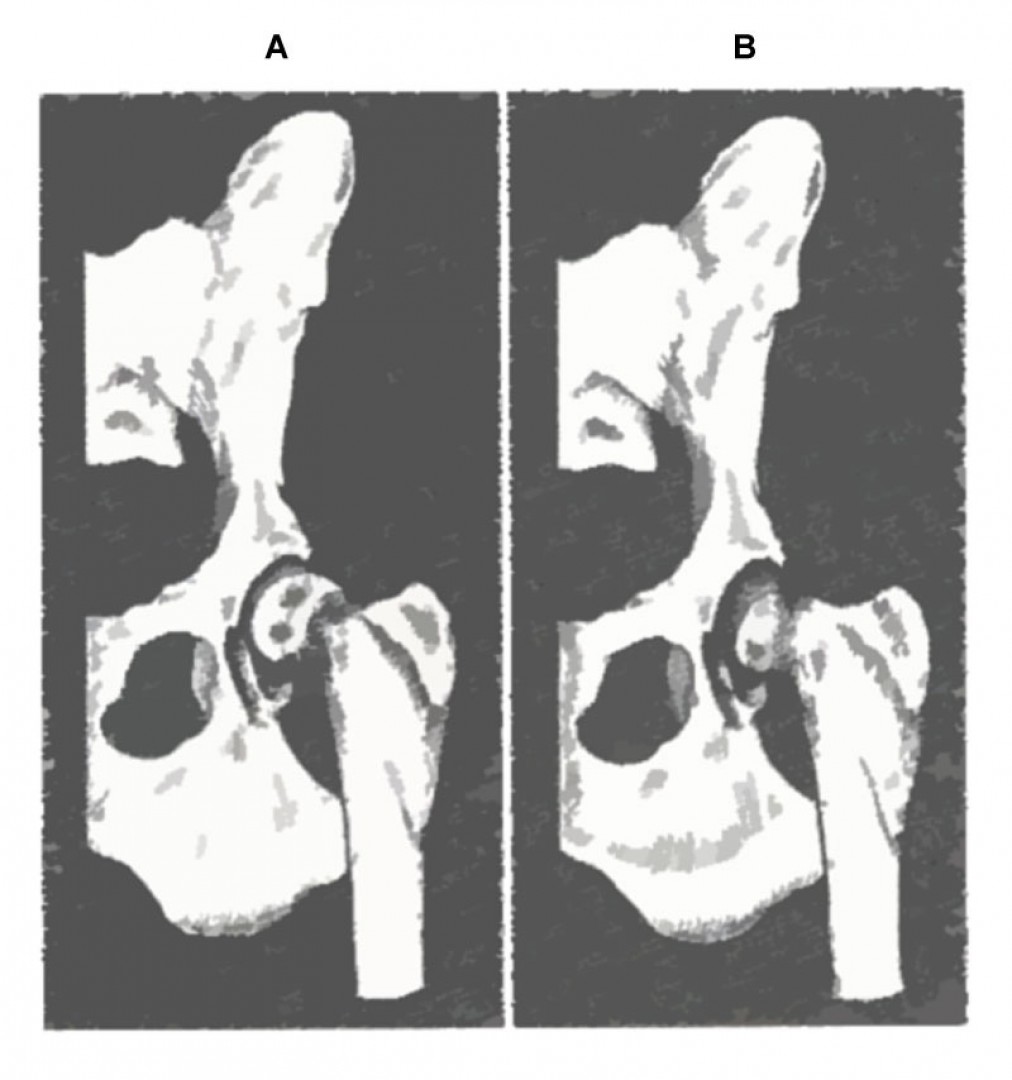

A röntgen felvétellel egyértelműen diagnosztizált betegség műtéti ellátást igényel. A beavatkozás során az elhalt combcsontfejet eltávolítjuk, megszűntetve az ízületi fájdalmat. A gyógyulási folyamat során a csípőízület helyén egy laza kötőszövetes kapcsolat alakul ki (álízület, pseudoarticulatio), mely fájdalommentes mozgást biztosít a medencecsont és a combcsont között.